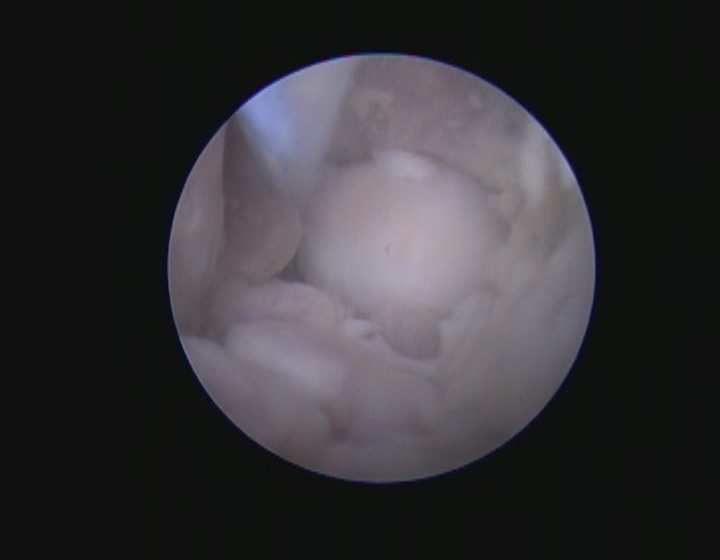

オトスコープ検査

オトスコープとは耳専用の内視鏡のことです。

オトスコープは耳道の奥まで明るく照らしながら観察できるため、従来の耳鏡では見えにくい部分も確認できます。

また耳道内に異物が入っている場合や腫瘤がある場合はオトスコープを用いることで早期に発見し、迅速に対処することが可能です。

オトスコープは得られた画像をモニターに写し、飼い主様と共有することで、耳道の状態や治療の必要性について理解を深めてもらうことができます。

特にオトスコープは、外耳や中耳内の徹底的な洗浄、ポリープや腫瘍の切除など幅広い処置が実施できます。

外耳炎の治療が長期化している、治ってもすぐに再発するなどの場合はオトスコープによる詳細な観察が有効です。